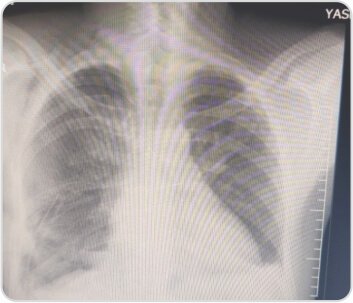

Post op chest X ray